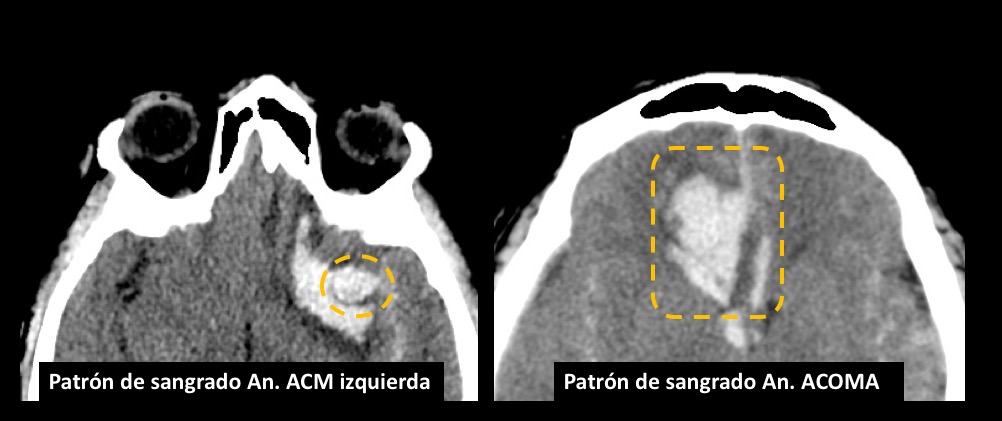

Fig. 1. TC de cerebro sin contraste: corte axial, evidenica HSA Fisher IV, Mayor espesor de HSA con hematoma asociado a nivel del valle Silviano izquierdo (circulo naranja). Volcado hemático ventricular en astas posteriores de ventrículos laterales (ver flecha).

Fig. 2. TC de cerebro sin contraste post tratamiento: corte axial, evidenica artefacto metalico por material de embolización a nivel del valle Silviano izquierdo (circulo naranja).

Fig 10. Hemorragia intraparenquimatosa en topografía de la arteria cerebral media izquierda (derecha) y hemorragia intraparenquimatosa en topografía de la arteria comunicante anterior (izquierda).

La edad de presentación y distribución del genero de los casos estuvo dentro del rango descripto en la literatura. La identificación del sitio correcto del aneurisma responsable del sangrado es posible en muchos casos, basada en la presencia de algunos signos presentes en la TC de cerebro simple inicial [51]. Siendo el signo más confiable, el espesor de un Coágulo >3mm localizado en el espacio subaracnoideo. También en algunas ocasiones se puede encontrar un centro hiperdenso dentro de la región de mayor cantidad de HSA, el cual representaría la localización del aneurisma responsable de la hemorragia. Otro signo importante, es el patrón de distribución de la hemorragia: por ejemplo, una gran cantidad de sangre dentro de la cisura interhemisférica y la cisterna supraselar comúnmente indica una ruptura de un aneurisma comunicante anterior (ACOMA) o del segmento A1 o A2 de la arteria cerebral anterior; Mientras que la sangre principalmente confinada a la cisura de Silvio se asocia con aneurismas de la bifurcación de la arteria cerebral media (ACM); Los sangrados a lo largo de las cisternas basales pueden señalar característicamente la ruptura de los aneurismas del TIP o del tronco basilar, así como también estos mismos sangrados con prevalencia hacia la derecha o izquierda con hemorragia intraventricular, pueden ser característicos de ruptura de aneurismas de la arteria cerebelosa posteroinferior (PICA).